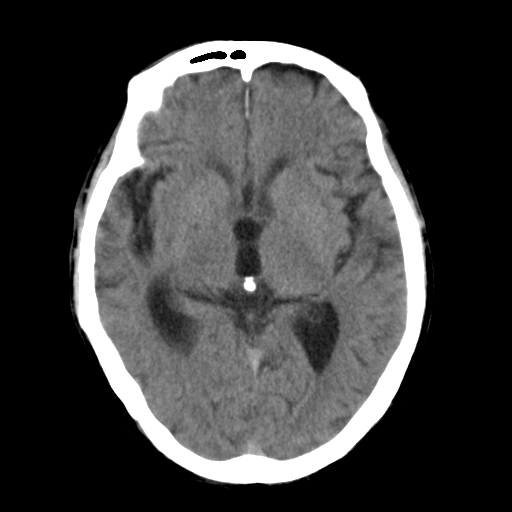

标题: CT25306:男性,75岁。右侧肢体无力一周。 [打印本页]

标题: CT25306:男性,75岁。右侧肢体无力一周。

右侧小脑楔形片状低密度影,考虑脑梗塞,建议mri或增强检查除外肿瘤占位

1)右侧小脑梗塞。2)脑萎缩。